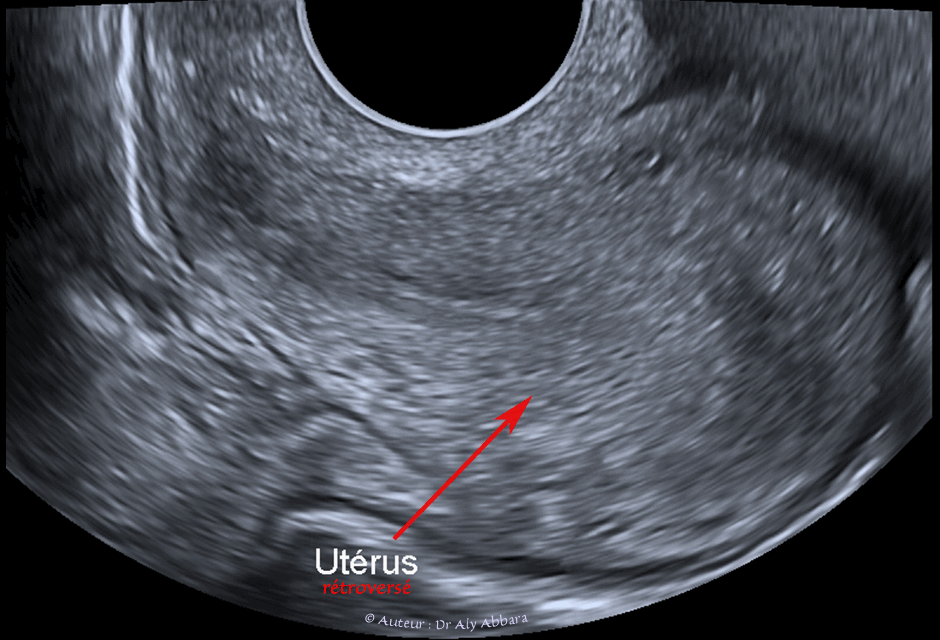

Image échographique du petit pelvis et de l'utérus montrant le reflux rétrograde, tubo-abdominal de sang menstrul (sang des règles)

Image clinique cœlioscopique animée, puis images échographiques par voie endovaginale (une coupe sagittale médiane sur un utérus rétroversé et une coupe longitudinale sur l'ovaire gauche) ; ces images illustrent le reflux rétrograde, tubo-abdominal de sang menstruel qui peuvent survenir au cours de certaines règles (menstruation ou menstrues rétrogrades).

Chez cette patiente, ce reflux menstruel tubo-abdominal assez important était à l'origine de règles extrêmement douloureuses (dysménorrhéique). Les douleurs pelviennes sont provoquées par l'irritation et la réaction inflammatoire du péritoine pelvien par le contact avec le sang de la menstruation qui a atteint la cavité péritonéale par voie rétrograde (cavité utérine > lumière de la trompe gauche > cavité péritonéale).